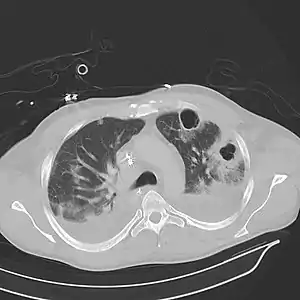

| Computed tomography (CT) scan of chest showing bilateral pneumonia with abscesses, effusions, and caverns. 37-year-old male. | |

Lung abscesses are often on one side and single involving posterior segments of the upper lobes and the apical segments of the lower lobes as these areas are gravity dependent when lying down. Presence of air-fluid levels implies rupture into the bronchial tree or rarely growth of gas forming organism.

Pulmonary abscess on CT scan

A subpleural abscess.